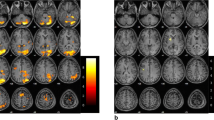

Maps of brain activation associated with imagery of foot and hand movements in the tetraplegic SCI subject after extensive BCI training. a Illustration of the possibility to use the BCI system to allow the patient grasping a glass with the paralyzed hand upon activation of a neuroprosthesis by EEG β-bursts of 17 Hz induced by foot movement imagination. These impulses are “translated” to hand/finger movements by functional electric stimulation (FES; with elbow movements accommodated by residual motor function by the patient). Brain activation maps associated with imagery of movement of the right (b) and left (c) foot and of the right (d) and left (e) hand relative to rest in the patient. Brain activation in expected somatopy in the primary sensorimotor cortex (SMC) contralateral to the side of imagined movement, supplementary and cingulate motor areas bilaterally and the cerebellum ipsilateral to the side of imagined movement becomes apparent (Z > 5.0; corrected P = 0.01; functional data overlaid on high resolution scans). These findings were confirmed by a model-free ICA-based exploratory data analysis (f–i). Brain activation elicited by active movement of the right foot (j) and dominant right hand (k) in the control group of five healthy age- and sex-matched subjects (Z > 5.0; corrected P = 0.01; functional data overlaid on mean high resolution scan). Substantial overlap in the activation patterns between the patient with covert and the controls with overt movement become apparent (compare to b and d, respectively). (All images shown in radiological convention; left side of the image is right side of the brain as indicated by “R” and “L”)

The SEPs and MEPs confirmed complete central conduction block in the tetraplegic patient. Contrasts of imagery of repetitive hand (Fig. 1b, c) and foot (Fig. 1d, e) movements versus rest in the patient demonstrated significant activation of sensorimotor networks similar to the patterns defined by contrasts of active movement versus rest in the healthy control group (Fig. 1f, g—data for left sided movement not shown as analogue to right sided movement; see Table 1 for MNI coordinates of significant clusters).

Significant activation was observed in clusters in the sensorimotor cortex (SMC) contralateral to the side of movement imagined in expected somatopy, in supplementary motor and pre-motor areas (SMA and pre-SMA), and in the cerebellum ipsilateral to the side of movement imagined, with differential activation for hand and foot movements (e.g. cerebellar lobules V, VI, and vermis for foot imagery versus culmen for hand imagery). In addition, significant activation was observed in bilateral occipital areas, attributable to processing of the visual cue. SMC and cerebellar activation was strongly lateralized depending on the side of movement imagined, i.e. located in the left cerebellum and in the right SMC upon imagination of left sided limb movements and vice versa (Fig. 1b–e). Independent component analysis confirmed the results of the model-based analyses (selected components shown in Fig. 1f–i).

Although involving identical components of the sensorimotor network, compared to active movement versus rest in the healthy controls, the peak activation in the SMC cluster with motor imagery in the patient tended to be shifted towards more cranial and anterior regions within the SMC (see Table 1 for cluster-coordinates and insets in Fig. 2). Also, the cerebellar activation peak associated with imagery of hand movements was located more caudally compared to active hand movement in the control, albeit it involved the same lobule.

Region of interest analyses demonstrating the extent of signal change in the primary sensorimotor cortices (SMC) in voxels with peak activation defined by motor imagery versus rest in the patient and by active movement versus rest in the controls. Insets show the clusters of activation comprising the SMC in coronal, sagittal and axial orientation with respective coordinates for imagery of movement in the patient (upper rows; designated by the label PC for patient cluster) and for active movement in the healthy controls (lower rows; designated by the label CC for controls cluster). The MNI coordinates of the PC and CC within the SMC were then used to compute the percent signal change versus rest at each of these locations for the respective contrasts. Grey columns indicate the signal change in the PC while the black columns indicate signal changes in the CC. a shows the results for the dominant right hand and b for the right foot, respectively. The following contrasts were generated: motor imagery versus rest in the patient (Patient), active movement versus rest in controls (Controlsmov), and motor imagery versus rest in the controls (Controlsimg). Further details are provided in the text

Motor imagery in healthy controls

Region of interest analyses

The coordinates of SMC peak activation associated with imagery of movement in the patient versus rest [insets designated as patient cluster (PC) in Fig. 2] and with active movement in the healthy control group versus rest [insets designated as control cluster (CC) in Fig. 2] were used to compute signal changes at ROIs for different contrasts, both for the dominant hands and feet (MNI coordinates in Fig. 2 indicating peak activation), in order to scrutinize in more detail for differences and similarities in SMC activation between the patient and the controls. With imagery of hand movement in the patient, the peak signal change in SMC was twice as high (2.18%; grey bar above designation “Patient”) compared to the signal change at the same ROI observed with active movement in the controls (1.05%; grey bar above designation “Controlsmov,” Fig. 2a). Signal change with imagery of hand movement in the patient at the ROI of peak activation associated with active movement in the control group (black bar above designation “Patient”; 0.70%) was similar to the magnitude of signal change observed with active hand movement in controls at the same ROI (0.81%; black bar above designation “Controlsmov”). Similar findings were noted for the foot area (Fig. 2b). Consistent with cluster-based statistics, only marginal signal change in both SMC ROIs were noted with imagery of foot or hand movement in the healthy controls (grey and black bars above designation “Controlsimg”).